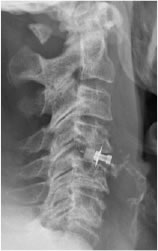

- discectomie antérieure avec mise en place d’une cage

- discectomie antérieure et mise en place d’une prothèse discale